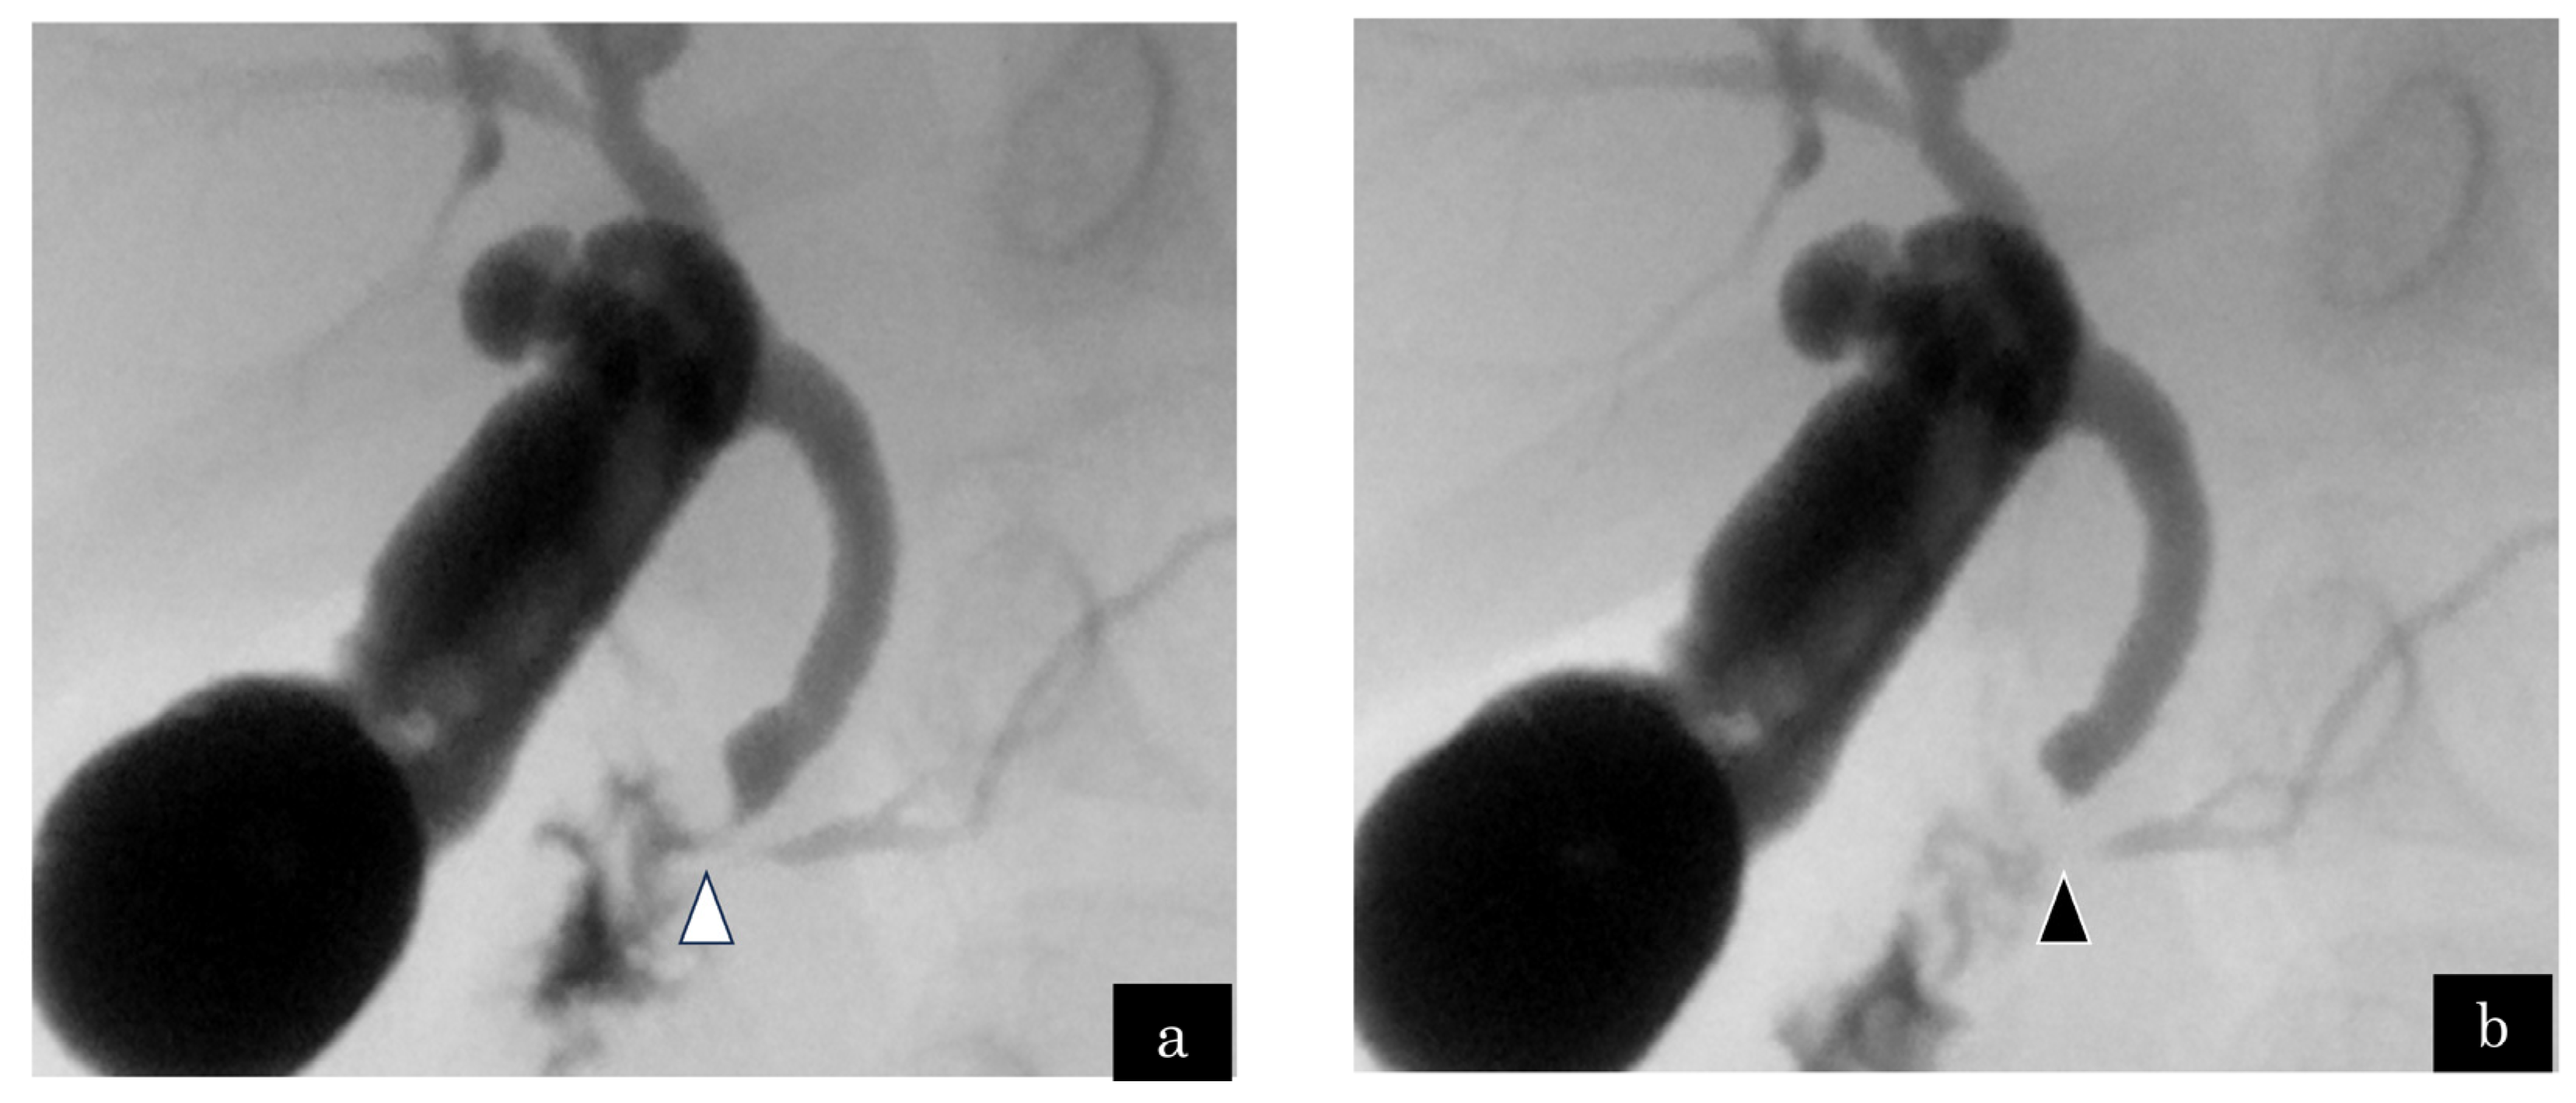

3.1.1. Case 1